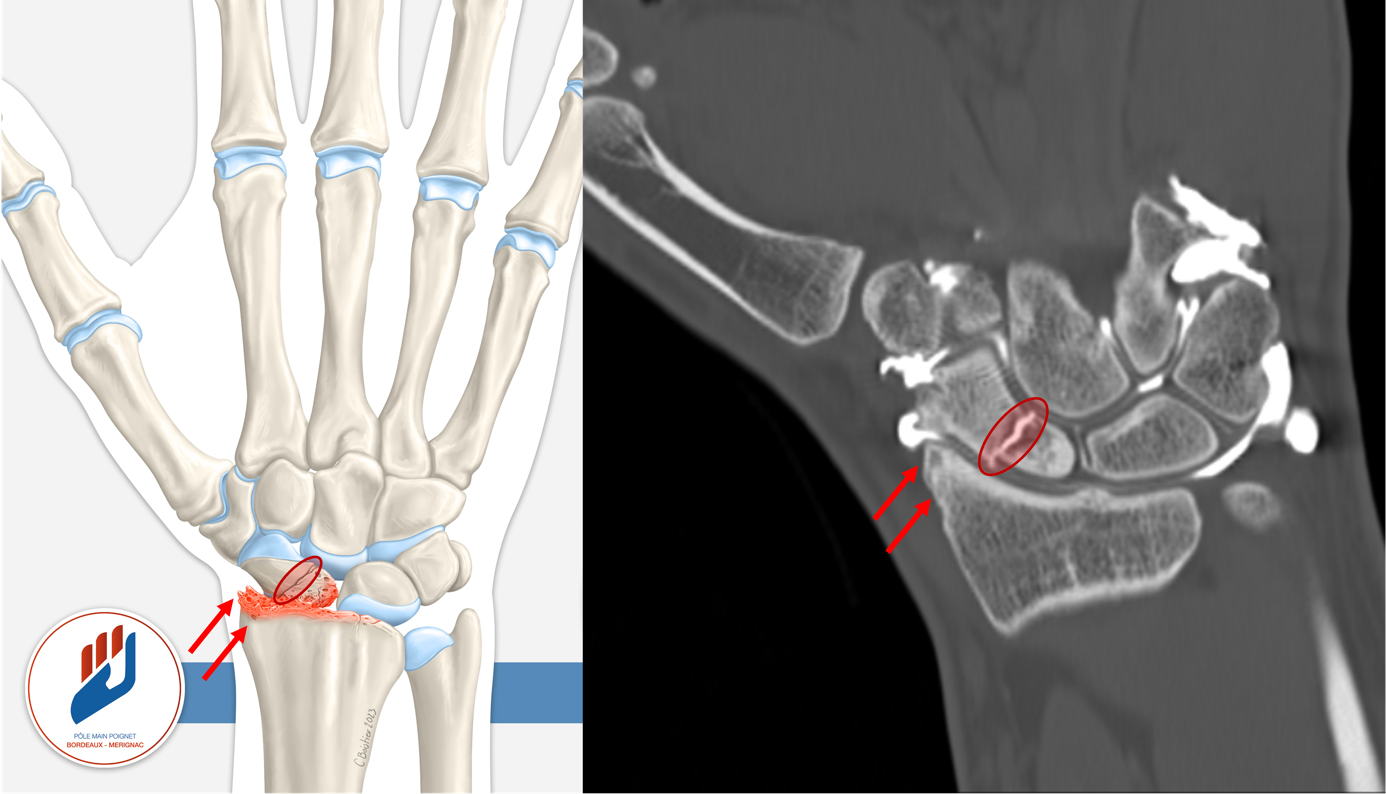

Le risque principal d’une fracture du scaphoïde est la non-consolidation, que l’on appelle aussi pseudarthrose (Voir article sur les pseudarthroses du scaphoïde). À long terme, cette situation peut entraîner un effondrement progressif de l’architecture du poignet, avec apparition d’une arthrose appelée SNAC wrist. Cette complication est irréversible et entraîne des douleurs chroniques, une raideur articulaire et une perte de force.

Lorsque cette situation évolue depuis plusieurs mois ou années, le traitement devient plus complexe. Des gestes de sauvetage comme des arthrodèses partielles du poignet, implant d’interposition, résection de la première rangée des os du carpe peuvent être proposés pour soulager les douleurs mais au prix d’une perte de mobilitée.